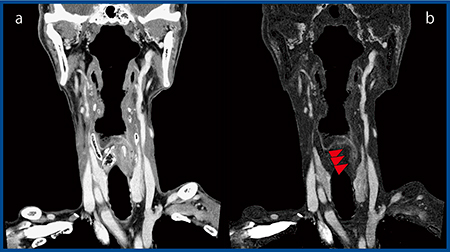

当施設では,2018年8月に超高精細CT「Aquilion Precision」を導入し,SURESubtractionを施行している。症例5は,76歳,男性の下咽頭がんで,術前化学放射線療法後の経過観察中である(図5)。Aquilion Precisionのコロナル画像では高い空間分解能により腫瘍が高精細に描出されている(図5 a)。

動きのある喉頭・咽頭においても,SURESubtractionによって高精度の差分が可能である(図5 b▶)。

図5 症例5:下咽頭がん(Aquilion Precision)

a:造影CT画像 b:SURESubtraction